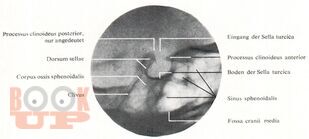

В учебном пособии представлены широкие возможности лучевых методов исследования при патологии области турецкого седла. Большое внимание уделено возможности классической краниографии с учетом новых современных аппаратов, таких как МРТ И КТ.

Подробно представлена классификация опухолей турецкого седла, их частота, клинические проявления с учетом физиологии гипофиза. Наряду с общепринятой классификацией с делением опухолей гипофиза на эозонофильные, хромофобные и базофильные варианты рекомендуется более современная классификация с делением аденом гипофиза по гормональной активности. Кратко даны возможности современных методов лечения опухолей области турецкого седла. Ценным являются представления о около селлярной локализации опухолей по топографической и гистологической структуре и генезу.

Методическое учебное пособие иллюстрировано снимками, схемами, дан краткий список литературы. Учебное пособие предназначено для интернов, ординаторов, рентгенологов.